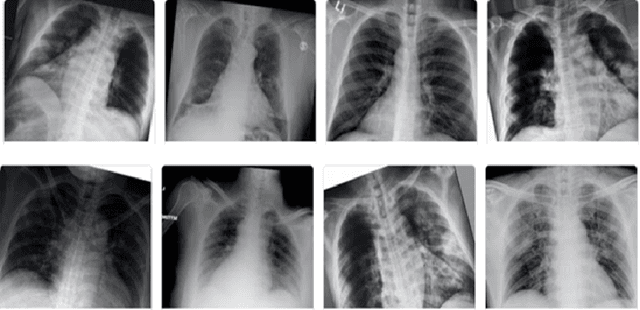

Abstract:Covid-19 detection at an early stage can aid in an effective treatment and isolation plan to prevent its spread. Recently, transfer learning has been used for Covid-19 detection using X-ray, ultrasound, and CT scans. One of the major limitations inherent to these proposed methods is limited labeled dataset size that affects the reliability of Covid-19 diagnosis and disease progression. In this work, we demonstrate that how we can augment limited X-ray images data by using Contrast limited adaptive histogram equalization (CLAHE) to train the last layer of the pre-trained deep learning models to mitigate the bias of transfer learning for Covid-19 detection. We transfer learned various pre-trained deep learning models including AlexNet, ZFNet, VGG-16, ResNet-18, and GoogLeNet, and fine-tune the last layer by using CLAHE-augmented dataset. The experiment results reveal that the CLAHE-based augmentation to various pre-trained deep learning models significantly improves the model efficiency. The pre-trained VCG-16 model with CLAHEbased augmented images achieves a sensitivity of 95% using 15 epochs. AlexNet works show good sensitivity when trained on non-augmented data. Other models demonstrate a value of less than 60% when trained on non-augmented data. Our results reveal that the sample bias can negatively impact the performance of transfer learning which is significantly improved by using CLAHE-based augmentation.